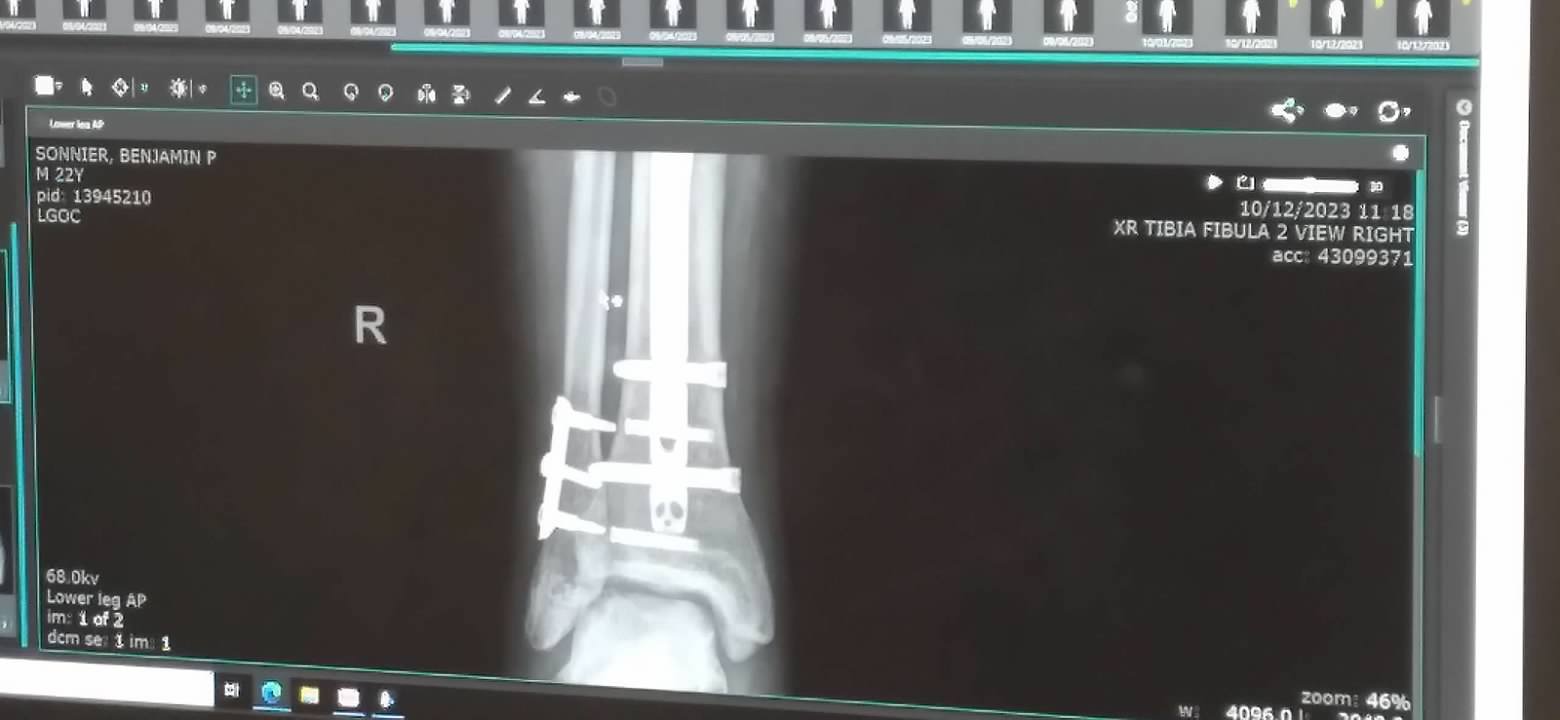

It was not to be.  As much as we wanted, the surgeon reported that there was bone loss and the tibia is a slow healing bone.  He wants Benjamin to remain off of the RT leg until November 13th.  He instructed us to give him Vitamin D and plenty of protein to encourage healing.  The x-rays show all the hardware in his right lower leg and ankle.  This is the first time we'd seen x-rays of the work done on his legs.